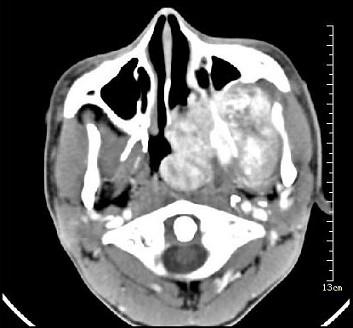

问题 男性,19岁,左侧鼻腔反复出血1年余,CT、MRI扫描如图所示,请选择最可能诊断()

选项 A.鼻息肉 B.鼻咽腔脓肿 C.鼻咽部青年纤维血管瘤 D.鼻咽癌 E.鼻咽部淋巴瘤

答案 C